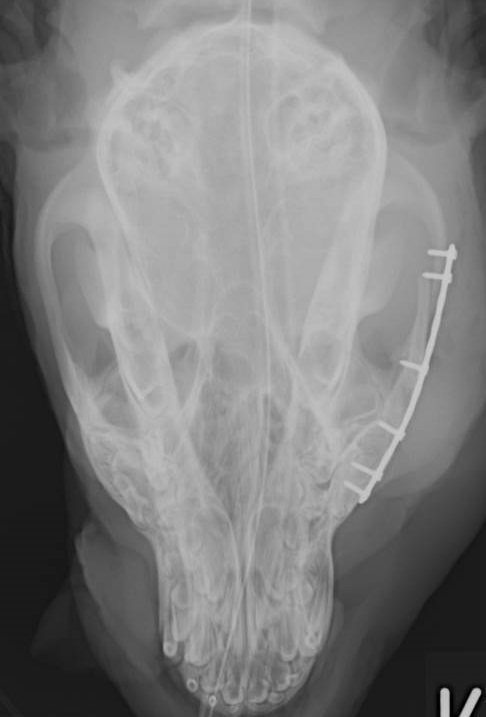

He was rushed to theatre where the bone was put safely back into position and to make sure it didn’t move, it was held in place with a bone plate and six screws (see below scan).